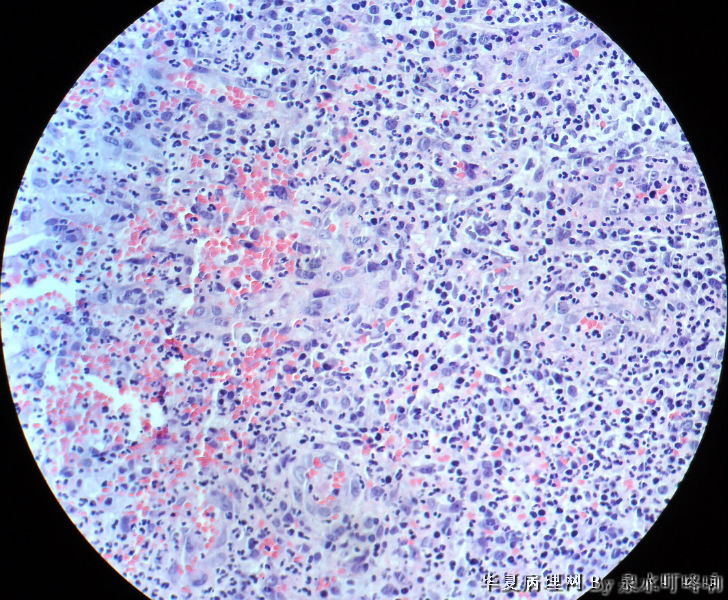

120071,男,64岁,左颊粘膜糜烂,面积约2×1.5厘米。